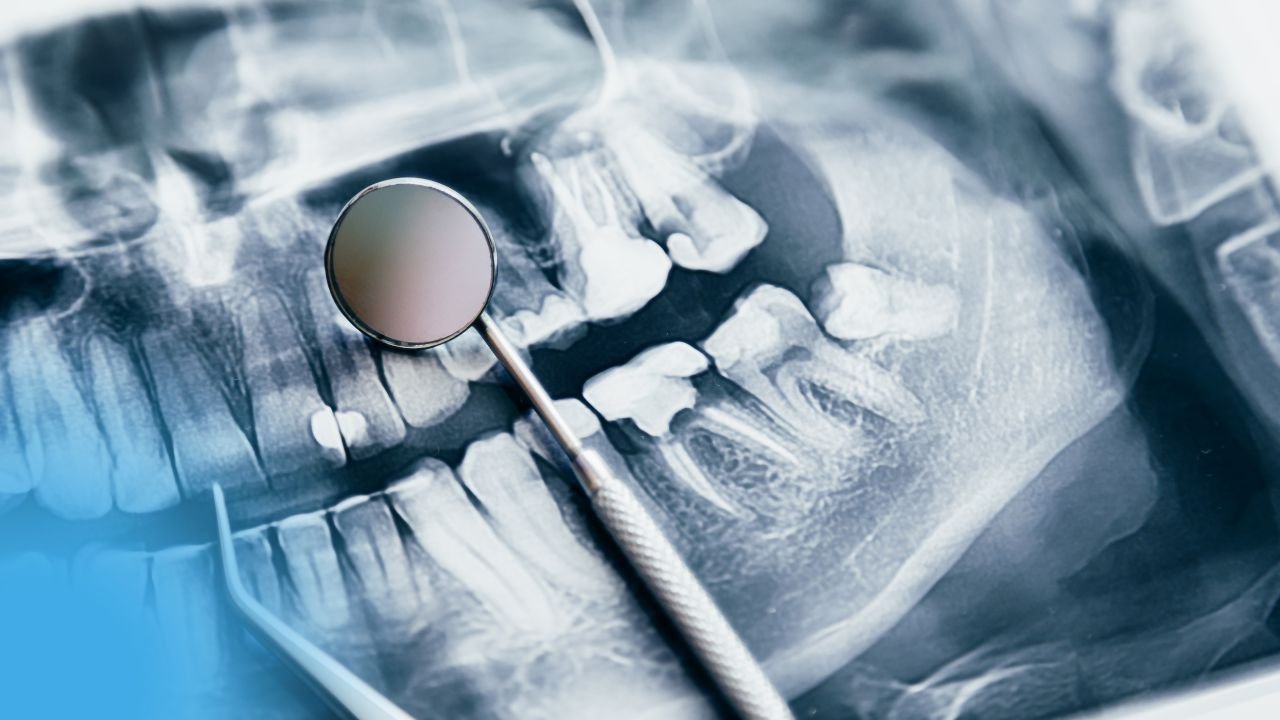

• Incidence radiologique en exploration dentaire .

• Cette incidence est dite incidence latérale oblique qui peut être

appliquée tant à la mandibule qu’au maxillaire.

• c’est une incidence complémentaire au panoramique dentaire

• Permet d’éviter la superposition des branches du maxillaire inferieur.